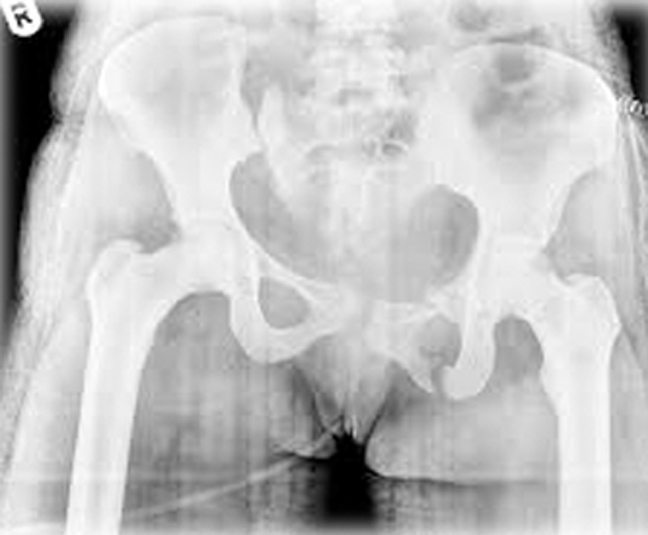

Το υπεξάρθρημα – διάσταση της ηβικής σύμφυσης σε πολύτοκες γυναίκες, συνήθως περνάει απαρατήρητο και διαγιγνώσκεται τυχαία σε ακτινογραφία. Μερικές φορές δημιουργεί ένα αίσθημα βάρους μπροστά στο εφηβαίο. Μπορεί να συνοδεύει κυστεοκήλη (δηλ. πρόπτωση του κόλπου).

Σε ακράτεια ούρων έχει παρατηρηθεί συνύπαρξη απλής διάστασης της ηβικής σύμφυσης που δεν σχετίζεται όμως βιβλιογραφικά με την ακράτεια.

Πώς ελέγχεται

Μόνο ακτινολογικά. Είναι τυχαίο εύρημα.